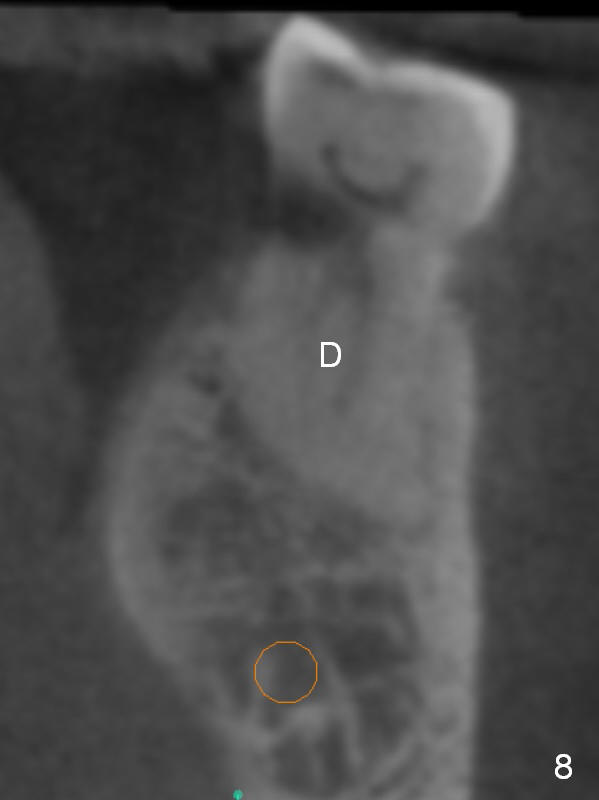

The shorter implant (10 mm (Fig.7 (coronal section)). as compared to 12 mm (Fig.6) more or less placed in the middle of the septum may decrease the chance to penetrate the coronal extension (Fig.8 brown triangle) of the Inferior Alveolar Canal (brown circle).

Coronal section through the distal root (Fig.8 D) shows that the lingual plate (Fig.9 (post extraction (Metronidazole)) L) looks thicker than the buccal one (B). When socket shield is performed in the distal root (Fig.10 *, surgical bur block with long surgical fissure bur), there will be less chance to place pressure on the thin buccal plate. The 6.9x10 mm implant may be oversized (Fig.11). Prepare DIO Sinus Master Kit so that 3-4 mm stoppers can be used for osteotomy.